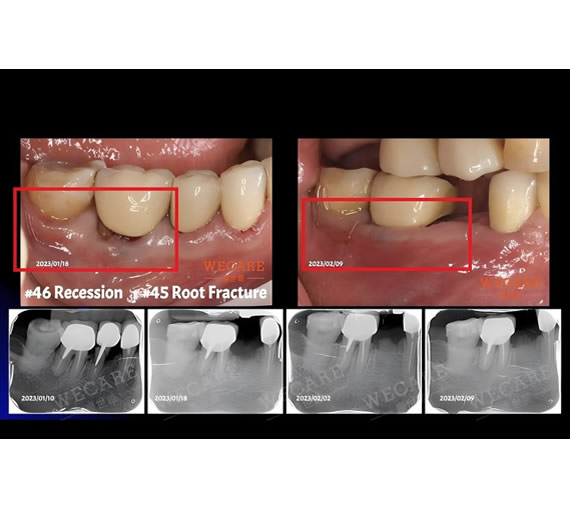

牙齦萎縮治療案例

牙齦萎縮指的是牙根不畏的牙齦萎縮,導致牙根暴露,影響口腔健康與美觀,且為很難完全恢復的症狀。牙齦萎縮較常見於中老年族群,但因口腔清潔狀況、齒列不整齊、飲食習慣等原因,近年牙齦萎縮、紅腫流血也有年輕化的現象。

您是否只要一吃到過冰或過熱的食物,牙齒就痠痛不適,讓美食體驗大打折扣?牙齒敏感絕大多數是因牙齦萎縮後牙根外露所致,萎縮的牙齦不但造成牙齒敏感、牙齦流血,也影響您笑容的美觀,且萎縮後的牙齦無法再回復,僅能細心維護不再持續惡化萎縮狀況。 藉由WECARE康世維的牙齦整形療程,能修復您暴露的牙根,讓您健康享受美食,展露自信微笑。

骨脊保存術

牙齒拔除後,原先牙齒週邊的齒槽骨失去了來自牙周韌帶的血液供應

在傷口縫合塑形的過程中,齒槽骨會漸漸吸收,尤其前牙區齒槽骨較薄,拔牙後萎縮塌陷的情形更為明顯。WECARE康世維在牙齒拔除的同時,進行骨脊保存術,將骨粉填入拔牙後的齒槽內以供支撐,減緩日後齒槽骨萎縮塌陷。